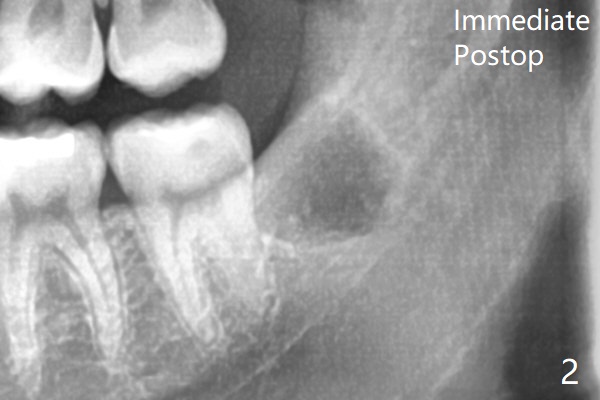

To prevent dry socket, collagen plug is placed at #17 and 32 post extraction (Fig.2).